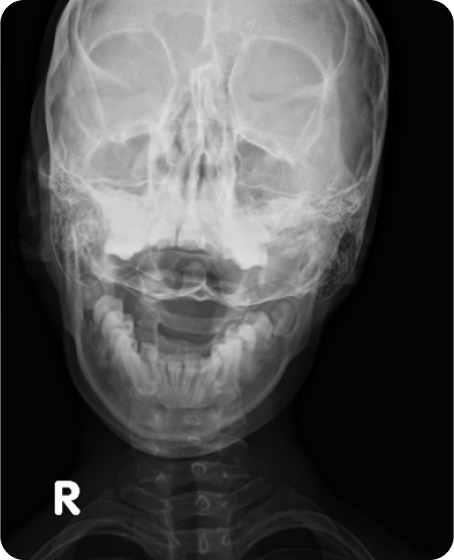

▲ CTA 9개월 착용 (2016년 10월 29일)